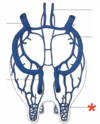

Mammary gland arrangement in swine

A

- Thoracic: 4

- Abdominal: 6

- Inguinal: 4

5

Q

Mammary gland arrangement in feline

A

Venous ring

26

External pudendal vein

27

Dorsal labial branch of the internal pudendal vein

28

Superficial epigastric vein

29

Venous ring